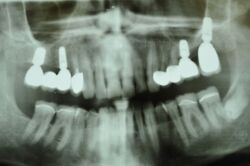

Alles siehgt perfgekt aus. 2 mm tiefe Taschen, perfekte Mundhygiene. Die Arbeit funktioniert!